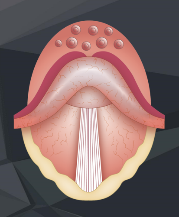

- Glottis

Die Glottis kann entweder ganz geöffnet, fast geschlossen oder ganz geschlossen sein.

ÜBUNG 2.1:

Strecke Deine Zunge heraus und atme mit weit offenem Mund durch diesen ein und aus. Fühle, dass die Stimmritze nun offen ist.

ÜBUNG 2.2:

Sage mit geöffnetem Mund „Aaaaaaahhhhhh“ und atme dabei durch den Mund ein und aus. Bei dieser Übung ist die Stimmritze durch die schwingenden Stimmbänder fast geschlossen.

ÜBUNG 2.3:

Strecke die Zunge heraus, atme durch den Mund ein und halte danach die Luft an. Fühle, dass dabei Deine Stimmritze beim Luftanhalten schließt und vollständig geschlossen ist.

Einatmung

Luft anhalten

Weicher Gaumen

Man kann sich die Stellung des weichen Gaumens durch folgende Übungen bewusst machen:

Geöffnete Stellung

Geschlossene Stellung

ÜBUNG 2.4.:

Atme mit geöffnetem Mund durch diesen ein und aus. Die Stellung des weichen Gaumens bleibt dabei offen. Anatomisch gesehen könnte die Luft auch durch die Nase entweichen. Da der Luftraum zum Mund jedoch viel weiter und größer ist, nimmt die Ausatemluft den Weg des geringsten Widerstandes durch den Mund.

ÜBUNG 2.5:

Atme einmal durch den geöffneten Mund ein und aus und danach bei geöffnetem Mund durch die Nase ein und aus. Fühle wie sich die Stellung Deines weichen Gaumens dabei verändert. Bei Nasenatmung ist der weiche Gaumen verschlossen, da der Luftstrom sonst den Weg durch den Mund nimmt.

Wir können uns die offene und geschlossene Stellung auch durch Sagen von „Bbbbbbb“ (weicher Gaumen offen) oder „Mmmmmm“ (weicher Gaumen geschlossen) bewusst machen.

- Zunge

Die Zunge kann den Mundraum in den vorderen und hinteren Mundraum unterteilen. Das ist an drei unterschiedlichen Stellen möglich und zwar durch das Sprechen der Buchstaben T (Verschluss vorne knapp hinter den oberen Zähnen), CA (Verschluss mittig) oder des arabisch gehauchten H (Verschluss hinten – geht auch mit CH)

Der sogenannte T-Verschluss kann auch mit den Buchstaben D oder N durchgeführt werden.

Beim Tauchen kann der Mund – bedingt durch das Mundstück des Atemreglers – nicht dicht verschlossen werden. Insofern wird beim Druckausgleich mittels Valsalva-Manöver immer eine der drei möglichen Verschlussarten (T, CA oder H) durch die Zunge benutzt um die Luft aus der Lunge vom hinteren Mundraum weiter in den Nasenraum zu drücken.

ÜBUNG 2.6:

Versuche einmal das oben abgebildete T-Verschluss-Valsalva-Manöver. Wenn Du es richtig durchführst, blähen sich bei zugehaltener Nase ganz leicht Deine Nasenflügel auf – ein Zeichen, dass Du es richtig gemacht hast. Spüre dabei, dass Deine Stimmritze offen bleibt!

ÜBUNG 2.7:

Beim Druckausgleich nach Frenzel mit Zunge in T-Stellung bleibt die Stimmritze geschlossen, da die Luft zum Druckausgleich nicht aus der Lunge kommt, sondern aus dem Mundraum nach oben in den Nasenraum gedrückt wird.

Bei beiden Techniken ist der weiche Gaumen natürlich offen!

Versuche beide Druckausgleichtechniken nun mit allen unterschiedlichen Zungenverschlüssen: T, Ca und H.

Sowohl beim Valsalva- als auch beim Frenzel-Manöver muss der weiche Gaumen natürlich offen sein und den Weg zum Nasenraum freigeben. Beim Valsalva ist die Stimmritze offen, beim Frenzel geschlossen (s. Bilder oben).